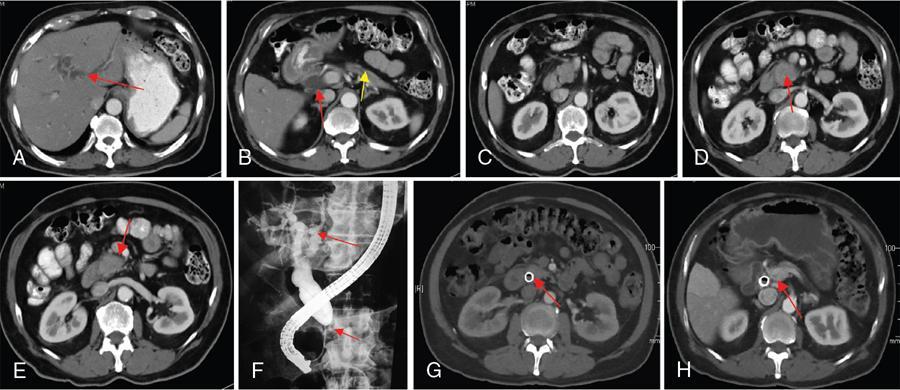

Ritu K. Kashikar, Shrinivas B. Desai, Chandresh Karnavat, Nilesh Doctor The biliary tract is subject to a variety of abnormalities. The spectrum includes benign diseases of autoimmune, infective, ischaemic, infiltrative aetiologies and malignant disorder, which most importantly represents cholangiocarcinoma. Imaging in particular magnetic resonance cholangiopancreatography (MRCP) plays a vital role in diagnosis and follow-up of these disorders. Multidetector computed tomography (MDCT) and magnetic resonance imaging (MRI) are also crucial in preoperative staging of biliary malignancies and making decisions regarding resectability and extent of resection. This chapter focuses on important benign and malignant disorders of the biliary tree and imaging features that aid in differentiation of various entities. A variety of disorders affect the biliary tree. Most biliary disorders manifest as biliary dilatation. The various causes are listed in Table 9.15.1. Imaging plays an important role in identification of aetiology based on pattern of involvement in association with clinical picture. USG is often the first investigation in a patient with jaundice. USG is excellent at showing biliary dilatation. It may be useless in assessing level of obstruction and biliary stones. Changes in liver morphology, development of cirrhosis is accurately done on USG. Early changes in conditions like primary sclerosing cholangitis (PSC), presence of intrahepatic ductal strictures, thickening of common bile duct (CBD) are, however, not confidently seen and need imaging modalities like MRCP and computed tomography (CT). Staging of hilar cancers is also best done on CT or MRI with contrast. Contrast-enhanced CT is extremely accurate in staging hilar cancers. It is a preferred modality to access radial spread of the disease and vascular involvement. Subtle changes of PSC and autoimmune cholangitis may however be missed and MRCP is preferred in these conditions. The protocol for evaluating biliary disease is standard plain scan followed by early, late arterial, portal venous and parenchymal phases similar to that obtained for focal liver lesions. Delayed phase images should be obtained for hilar malignancies, which often show delayed enhancement. MRCP with or without contrast is the modality of choice in diagnosing and characterizing biliary diseases. Owing to its noninvasive nature, it has replaced endoscopic retrograde cholangiopancreatography (ERCP) in the initial evaluation and follow-up of a variety of biliary pathologies. Absence of radiation exposure makes it suitable to obtain follow-ups in patients requiring serial scanning. The ability to diagnose abnormalities of both intra- and extrahepatic biliary tree, level of obstruction, longitudinal and radial spread of neoplastic process make it an ideal modality. MRCP protocol includes T2 weighted single-shot fast spin-echo, T1 weighted in phase and opposed phase gradient echo, diffusion-weighted imaging, T2-weighted fat-suppressed fast spin-echo in axial and coronal. A pre contrast three-dimensional T1-weighted fat-suppressed spoiled gradient-echo image is obtained in addition to 3-D MRCP. Postcontrast protocol includes dynamic three-dimensional T1-weighted fat-suppressed spoiled gradient-echo (in arterial, late arterial and portal venous, parenchymal and delayed phases). Since the advent and widespread use of MRCP, the utility of ERCP in diagnosing biliary pathologies has significantly reduced. ERCP is primarily used when stenting or other procedures need to be performed in the same setting. Although an invasive procedure with postprocedural risk of pancreatitis ERCP allows excellent depiction of biliary changes in conditions like PSC, recurrent pyogenic cholangitis (RPC) and IgG4-related disorders. Endoscopic USG (EUS) is an excellent modality in diagnosing lower bile duct pathologies and also has the added advantage of obtaining a biopsy in the same setting. EUS is less invasive than ERCP and overall safer. PSC is a premalignant cholestatic liver disorder characterized by bile duct strictures secondary to bile duct inflammation and fibrosis. Cirrhosis of liver can develop secondary to this condition and patients are at a high risk for biliary and colonic cancers. PSC is a relatively rare disease, with an incidence of less than 50 per 100,000 patients though it varies in various location. It is diagnosed in young patients aged 30–40 years and is twice as common in men than in women. Similar to other autoimmune diseases, genetic susceptibility is likely to be instrumental in the development of PSC after exposure to a trigger. There is also a strong association between PSC and human leukocyte antigens (HLAs). Environmental factors such as childhood microbial exposure also play an important role in disease pathogenesis. A strong association of PSC with inflammatory bowel disease (IBD) is seen. There is a 100-fold increased risk of developing PSC among siblings. PSC can be asymptomatic but may present with cholestatic symptoms such as jaundice, pruritus, fatigue and right upper quadrant pain, steatorrhoea and episodes of acute bacterial cholangitis. There is marked elevation of alkaline phosphatase (ALP). A twofold to threefold increase in serum alanine and aspartate aminotransferase (AST) can be seen. Elevated bilirubin is usually seen in advanced disease, malignancy or those with choledocholithiasis. Various serum antibodies can also be elevated in PSC. These have been enlisted in Table 9.15.2. On liver biopsy, classic pathologic features of periductal concentric fibrosis or ‘onion skin’, around the affected ducts can be seen. This is however not a pathognomonic finding and is seen in less than 40% of biopsy specimens. Therefore, biopsy is not routinely used as a diagnostic tool for PSC and is reserved primarily for disease staging. MRI with MRCP best depicts the biliary changes in PSC and is the modality of choice. While CT and USG may show biliary dilatation and changes of cirrhosis in advanced cases, they fail to show early changes (Table 9.15.3). USG is an effective modality for the visualization of dilatation and diffuse wall thickening of the extrahepatic bile duct. Other feature seen on USG is bright echogenic portal triad. However, the role of USG in the diagnosis of early PSC is limited owing to suboptimal assessment of the intrahepatic biliary ducts. Features of advanced disease such as heterogeneous coarse echogenicity can be readily detected with USG. The major benefit of performing US is to guide liver biopsy. Also, liver stiffness as assessed by transient elastography correlated well with the degree of liver fibrosis in PSC patients. CT can demonstrate some findings suggestive of sclerosing cholangitis such as focal, discontinuous, often peripheral intrahepatic biliary duct dilatation and thickening with enhancement of the bile ducts owing to inflammation. CT is effective in helping exclude other causes that can result in biliary stasis and dilatation such as hepatic and pancreatic lesions. CT is also excellent in diagnosing tumours, which may sometimes have similar presentation. Concomitant changes of IBD, if present, can be seen. However, CT is limited in assessment of biliary strictures and visualization of disease involving small peripheral bile duct, especially in the early stages of the disease. CT shows changes of cirrhosis in liver and assessing changes of portal hypertension. MRCP is diagnostic imaging modality of choice in the workup of patients with suspected PSC, as recommended by both the AASLD and EASL guidelines. MRCP has high diagnostic sensitivity (86%) and specificity (94%) for the detection of PSC (Table 9.15.3). Multifocal short segmental strictures in the intra- or extrahepatic biliary tree with intervening normal or dilated duct leading to beaded appearance are seen in early disease. The location in strictures is usually at the biliary bifurcation and are disproportionate to upstream dilatation. Advanced cases show pruning of peripheral biliary radicals secondary to advancing fibrosis obliterating the smaller ducts. An obtuse angle between the central and peripheral ducts is suggestive of PSC. Diverticula and webs also can be seen, though not pathognomonic (Table 9.15.4) (Figs. 9.15.1–9.15.3). Strictures of the CBD of less than 1.5 mm and of left, right or common hepatic duct (CHD) of less than 1 mm are defined as dominant stricture. A dominant stricture is associated with worse prognosis in part due to development of cholangiocarcinoma. MRCP plays an important role in raising the suspicion and guiding treatment. A dominant stricture may be confused with hilar cholangiocarcinoma on imaging and it is often impossible to distinguish the two based on imaging alone (Table 9.15.4) (Fig. 9.15.4). Changes in liver morphology are seen in the form of distortion. The classical change described in PSC includes hypertrophy of the caudate lobe and atrophy of the left lateral and right posterior segments of the liver. Hypertrophy of caudate lobe is more frequent in PSC than cirrhosis from other aetiologies. Other parenchymal changes include heterogeneity of liver, periportal cuffing, peripheral inflammation, cirrhosis and features of portal hypertension. Hyperintensity of the liver parenchyma in PSC on nonenhanced T1-weighted images has been reported. Wedge-shaped peripheral atrophic areas of confluent hepatic fibrosis are seen as high T2-weighted signal intensity. Periportal oedema is visualized as high signal intensity in periportal region on T2-weighted. Increased heterogeneous peripheral enhancement of the liver parenchyma can be seen and is likely due to the altered blood supply in those areas in response to parenchymal inflammation (Table 9.15.4) (Figs. 9.15.5 and 9.15.6). MR elastography is the most accurate noninvasive method for the diagnosis and staging of liver fibrosis and could potentially replace liver biopsy. It is predictive of progression to decompensated liver disease. However, lack of wide availability are still major limiting factors. MR elastography is not influenced by obesity or anatomical conditions (e.g. narrow intercostal spaces and ascites) and the sample size of the liver is significantly higher and hence has several advantages over ultrasound elastography (Table 9.15.5). Besides these features, enlarged reactive abdominal lymph nodes, commonly periportal and portocaval lymph nodes, are commonly diagnosed in PSC and should not be misdiagnosed as a lymphoproliferative disorder or metastatic disease. Though ERCP has higher diagnostic accuracy in detecting PSC, its role is limited to intervention required in PSC due to its invasive nature and potential complications. Also it is recommended that MRCP be performed prior to ERCP as a preprocedural MRCP can provide a road map to the endoscopist. Small duct PSC is a variant PSC syndrome with biochemical markers and histologic features suggestive of PSC with normal cholangiography. It is associated with better prognosis. Approximately one-fourth of patients’ progress to classic PSC in an average of 8 years. Bile duct calculi are a common complication of PSC. Pigmented bile duct stones are common owing to biliary stasis. Both intrahepatic and extrahepatic biliary stones can be found. However, the presence of biliary tree stones is not an essential diagnostic feature. Soft calcific foci within dilated bile ducts can be seen on US and CT images. MRI with MRCP is the imaging modality of choice to detect bile duct stones and appear as focal areas of signal-intensity-void filling defects on T2-weighted images. Usually isointense at T1-weighted imaging but frequently are hyperintense. The presence of biliary strictures puts these patients at risk of bacterial cholangitis in PSC patients. The classic Charcot triad of fever, abdominal pain and jaundice can be seen. Early enhancement of the biliary wall due to the biliary duct inflammation is a common finding with peribiliary reactive hepatic parenchymal changes. Cholangitic abscesses may sometimes be seen. PSC patients are at high risk of developing cholangiocarcinoma during the disease course with and a total risk of 10%–15%. Approximately 30% of all cholangiocarcinomas are detected within the first year of establishing a diagnosis of PSC and so it is important to be suspicious even at the time of PSC diagnosis and to survey for early detection. Rapid clinical deterioration, worsening of jaundice, pruritus, weight loss along with elevation in serum bilirubin and ALP should raise suspicion of PSC. It may be difficult to distinguish benign from malignant strictures. Progressive bile duct wall thickening, irregularity, enhancement, new onset biliary dilatation, dominant stricture or development of focal strictures with dilatation and ipsilateral atrophy are indeterminate features that may raise possibility if occult cholangiocarcinomas. Perivascular thickening, vascular involvement or occlusion are features favouring malignancy. Definite diagnosis is however often not possible on imaging alone and a brush biopsy should be taken in patients with new onset clinical symptoms, elevated tumour makers or above-mentioned indeterminate imaging features (Table 9.15.7). The most common subtype of cholangiocarcinoma in PSC patients is periductal type, characterized by long segment irregular wall thickening along the bile duct with no identifiable mass. The lesion is hypointense on T1W1 images and hyperintense on T2W1 images showing progressive enhancement on contrast study. The tumour could be at the bifurcation and can cause abrupt cut-off, commonly presenting as Klatskin tumour (Fig. 9.15.7). Combined UC and PSC is associated with a higher risk for colorectal carcinoma than UC alone. PSC is considered as an independent risk factor for development of colorectal carcinoma in patients with UC. Malignancy tends to involve the right colon or more proximal parts of the colon. Clinical presentation and history in patients with ascending cholangitis differ from those with PSC. Fever, pain and jaundice dominate the presentation in patients with ascending cholangitis while patients with PSC may be asymptomatic. The typical findings of PSC including biliary duct stenosis, beading or pruning are not typical findings in the newly diagnosed cases of acute ascending cholangitis. Wedge-shaped peripheral and/or intrahepatic peribiliary foci of increased T2 signal around the dilated radicals with arterial and/or delayed parenchymal enhancement has been described in ascending cholangitis. Patients with RPC present with recurrent episodes of abdominal pain, fever, jaundice and chills. These features differ from those in patients with PSC. Hepatolithiasis with pigmented stones in the biliary tree and upstream and downstream duct dilatation are typical imaging features in RPC (Table 9.15.8). Ischaemic cholangiopathy is a form of biliary injury resulting from decreased arterial supply. History of liver transplantation is the key in diagnosing ischaemic cholangiopathy. Biliary strictures in AIDS cholangiopathy are indistinguishable from PSC. However, the combination of papillary stenosis and intrahepatic ductal strictures appears relatively unique to AIDS cholangiopathy; this combination is not found in PSC. Clinical history may help to distinguish one from the other. Effective medical therapy for PSC is lacking. Oral ursodiol (ursodeoxycholic acid) is one of the main treatment options of cholestatic diseases though does not prevent disease progression. Azathioprine and steroids are recommended for use in patients with AIH as well as those with AIH–PSC overlap syndrome. Vedolizumab is a gut-specific monoclonal antibody that has been tried but the clinical utility in PSC–IBD patients remains under investigation. Dilatation of biliary strictures, stenting, lithotripsy and stone extraction can be done with the aid of ERCP and percutaneous transhepatic cholangiography (PTC). The only definitive cure of PSC is, however, liver transplantation. Treatment of complications like choledocholithiasis stone removal can be accomplished by using standard endoscopic techniques with or without sphincterotomy, with balloon or basket extraction for extrahepatic biliary stones. For bacterial cholangitis, immediate administration of broad-spectrum antibiotic therapy is recommended and in abscess formation percutaneous drainage with intravenous antibiotic therapy shows favourable outcome compared with surgical drainage. Incidence is 20%–25%. Diagnosis of recurrent PSC requires careful evaluation, as there are other causes of biliary changes after liver transplant with similar features. Nonanastomotic biliary strictures imply the diagnosis of recurrent PSC only if they occur more than 90 days after transplant. Characteristic multifocal strictures and segmental dilatations of biliary ducts are suggestive findings. MRCP is the initial modality. RPC is characterized by a triad of recurrent biliary sepsis, inflammatory biliary strictures and intrahepatic stones. Fifty per cent of patients may have acute pancreatitis. Oriental cholangiohepatitis, primary hepatolithiasis, Hong Kong disease and oriental infestational cholangitis. Prevalence in the third and fourth decades of life with equal frequency among men and women peak. Southeast Asia predominantly in rural population and in lower socioeconomic groups. Gut-derived organisms lead to sepsis, which initiates a cascade of events, which leads to a chronic, progressive and recurrent inflammatory process in cholangioles. Associations with Clonorchis sinensis, Opisthorchis species, Fasciola hepatica and Ascaris lumbricoides infestations have been suggested. Common organisms cultured from bile include Escherichia coli, Klebsiella, Pseudomonas and Proteus species and anaerobes. Structural biliary abnormalities may develop before stones are demonstrable. Strictures may be seen at cholangiography without stones and vice versa. Entrapped stones cause stasis, sepsis, scarring and stricturing with the increasing lithogenicity (Table 9.15.9). Typically present with abdominal pain, fever and jaundice (the Charcot triad) and commonly provide history of repeated episodes. Routine investigations may demonstrate leukocytosis, deranged liver enzymes with obstructive pattern. Elevated cholestatic markers (bilirubin, ALP and gamma GT) and deranged LFTs can be seen. Serum inflammatory markers can be elevated. Additional tests aiding in differential diagnosis include autoantibodies, ANCA, CA19-9 and serologic tests for Echinococcus. Histology is usually not required. It shows fibrous mural thickening of bile ducts and periductal tissue, as well as acute and chronic inflammatory changes. The imaging features include changes in bile ducts, development of calculi and changes in the parenchyma. The disease affects intrahepatic ducts more than the CHD and CBD. Disproportional dilatation of central intrahepatic ducts and extrahepatic bile ducts is seen with nondilated or minimally dilated peripheral ducts, leading to abrupt tapering of bile ducts. All segments of biliary tree may be involved, but the lateral segment of the left lobe is most often and extensively involved most likely because left hepatic ducts come off at a more acute angle compared with the right hepatic ducts, thus predisposing to stasis and stricture formation (Table 9.15.10). Hepatolithiasis is common in patients with RPC. Stones are composed mainly of bile pigments with variable calcification. There may be single or multiple stones scattered in the intra- or extrahepatic ducts or both. The dilatation of the extrahepatic duct is generally not related to the location of the stone. Ducts both proximal and distal to the stone are dilated. Parenchymal atrophy most commonly involves the left lateral and right posterior segments while hypertrophy of the caudate and right lobe is seen. USG shows dilatation of the central intrahepatic and extrahepatic ducts, with relative sparing of the peripheral biliary tree. Hepatolithiasis can be seen in 90% of cases. The echogenicity and acoustic shadowing of calculi may vary depending on extent of calcification. There is often associated periportal echogenicity. Ultrasound may be useful in performing image-guided percutaneous drainage of abscesses or biopsy of suspicious lesions. Limitations include inability to detect subtle intrahepatic ductal dilatation and heavy stone burden obscuring evaluation of underlying hepatic parenchyma. Contrast-enhanced CT is increasingly being used as first line of imaging. It allows for detection of characteristic disproportionate dilatation of the extrahepatic and central intrahepatic ducts. Contrast-enhanced CT also allows for detection of bile duct wall enhancement, suggestive of acute cholangitis. Ninety per cent stones are hyperdense to liver parenchyma on nonenhanced scan. Extent of calcification in calculi may vary. Parenchymal atrophy affects left lateral segment most frequently, followed by right posterior segments. Eventually, changes of cirrhosis can be seen. Heterogeneous appearance of liver parenchyma with segmental steatosis and altered enhancement can be seen particularly during acute attack. Pneumobilia is not infrequent and can usually be attributed to recent procedures or surgeries like bilioenteric anastomosis. It may, however, be seen in patients without history of prior interventions due to recent passage of stone through the ampulla or less commonly cholangitis related to gas forming organisms (Fig. 9.15.8). Subtle intrahepatic ductal strictures and noncalcified stones may be missed on CT. MRCP allows visualization of both intra- and extraductal disease and can reveal complete extent, severity and complications of the disease. Even noncalcified calculi which may be missed on CT or sonography, are seen as intraductal filling defects on heavily T2-weighted images and may appear hyperintense to the liver on T1-weighted images. MRI demonstrates central and extrahepatic duct dilatation with decreased arborization and abrupt tapering of peripheral ducts. MRI particularly MRCP sequences accurately depicts stenotic segments and delineates the entire biliary tree, including the proximal part of the stricture, without risk of aggravating biliary sepsis. Even short segment duct strictures <1 cm are easily seen on MRCP (Figs. 9.15.8 and 9.15.9). Parenchymal abnormalities like hepatic atrophy, whether diffuse or segmental, and altered signal can be accurately diagnosed. Mass lesions and hepatic abscesses, if present, are also well delineated. The characteristic finding of disproportionate dilatation of the ducts, with multiple intraductal calculi are well demonstrated. There may also be intrahepatic strictures, with abrupt tapering of the peripheral ducts as well as decreased arborization of the biliary tree (arrowhead appearance). It allows for better spatial resolution, thus permitting better evaluation of the smaller peripheral ducts. The main limitation of ERCP is its invasive nature, with complications such as ERCP-associated pancreatitis. Heterogeneous parenchymal enhancement, wall thickening and periductal enhancement are seen in acute cholangitis. Abscess formation is encountered in up to 20% of RPC patients who undergo cross-sectional imaging. The abscesses can occur in both the affected and unaffected portions of the liver but most commonly seen in the right lobe. Sonography guided aspiration can be done when diagnosis is doubtful. Intrahepatic bile lakes are not infrequent and may or may not communicate with the biliary tree. On USG bilomas appear anechoic and are usually hypodense on CT with or without calculi. Leakage of bile from a severely dilated obstructed duct may lead to formation of extrahepatic biloma. Cholangiocarcinoma is the most feared complication and may be seen in up to 5% of patients. Segments with high stone burden or those with atrophy are more prone to developing cholangiocarcinoma. Clinical and laboratory indicators for development of cholangiocarcinoma in patients with PSC include increase in jaundice without associated cholangitis, sudden weight loss, significant elevation of ALP and rising tumour markers. Peripheral cholangiocarcinoma manifests as expansion of the affected segment. Hypoattenuating mass with showing peripheral enhancement causing narrowing of the portal vein may raise suspicion of malignancy. Portal vein thrombosis has also been reported but is rare. Recurrent biliary sepsis may lead to periductal inflammation and portal thrombophlebitis. Portal thrombosis can lead to lobar atrophy with compensatory hypertrophy of the uninvolved lobe. Higher incidence of hepatocellular carcinoma (HCC) is reported in patients with RPC due to development of cirrhosis in severe cases. Management should comprise antibiotic treatment, clearance of stones, maintenance of biliary drainage and long-term follow-ups. ERCP allows for therapeutic procedures such as stone removal and stenting of strictures. Destroyed liver segments, those with multiple abscesses and patients with secondary cholangiocarcinoma are candidates or surgery. Stone extraction can also be done surgically with the aid of basket, forceps, balloon catheter or flexible choledochoscope. Transduodenal sphincteroplasty and hepaticojejunostomy are commonly performed drainage procedures. Indications for transplantation include extensive bilobar hepatolithiasis, cirrhosis and liver failure. IgG4 cholangiopathy is a cholangitis characterized by elevated serum IgG4 and infiltration of the bile duct wall with IgG4 positive plasma cells leading to storiform fibrosis and obliterative phlebitis with resultant bile duct wall thickening. This condition shows good response to steroids. Frequent association with IgG4-related autoimmune pancreatitis is seen. IgG4 sclerosing cholangitis (IgG4-SC) has a threefold to fivefold higher prevalence in men than women. It usually presents in the fifth and sixth decades of life. Incidence of this disease is approximated to be around 0.28–1.08/100,000. Autoimmunity has been considered as the most probable pathogenesis of IgG4-related disease (IgG4-RD). Several HLA association have identified as determinants of disease susceptibility. The major histologic features associated with IgG4-RD have been well described and include the steps. Chronic or recurrent cholangitis is the most common presentation and seen in up to 75% cases. Other symptoms seen are fever, pruritus, pain and weight loss. Biliary involvement may be detected incidentally in patients being scanned for symptoms related to involvement of other organs such as pancreas. One-quarter of patients with IgG4-SC may be asymptomatic. Serum liver tests show a cholestatic pattern with often marked elevation of ALP and γ-GT and only mildly increased ALT and AST. Serum bilirubin may be increased. Tumour marker CA 19-9 is not able to distinguish pancreatobiliary malignancies from IgG4-SC since levels of >1000 IU/mL (ULN = 37 IU/mL) may be observed in IgG4-SC. IgG4 levels are elevated (>140 mg/dL) in up to 75%–80% of affected patients. A cut-off level of 207 mg/dL might be useful for completely distinguishing IgG4-SC from cholangiocarcinoma. Elevated bile fluid IgG4 has a high sensitivity and specificity of 100% at a cut-off level of 113 mg/dL and seen only in cases of IgG4-RD, neither PSC nor cholangiocarcinoma. Approximately 40% of patients have peripheral blood eosinophilia, often accompanied by asthma and atopy. Patients may show hypergammaglobulinemia, elevated serum IgE. Several diagnostic criteria have been developed to aid in the diagnosis of IgG4-SC. The most widely used is the HISORt (Histology, Imaging, Serology, other Organ involvement and Response to therapy) criteria of the Mayo Clinic. This tool was initially used to diagnose AIP but can be adapted to diagnose IgG4-SC by Ghazele et al. (Tables 9.15.13 and 9.15.14). It is often the initial investigation and may be normal early in the course of the disease. Circumferential thickening of the bile ducts with biliary dilatation is seen later in the disease. US also helps in the identification of associated findings affecting other organs. However, US has low sensitivity in detecting the disease and is suboptimal for assessing the extent of the disease. Contrast-enhanced CT though not the investigation of choice shows bile duct wall thickening with proximal mild dilatation. The intrapancreatic bile duct segment is more commonly involved. The most important finding is circumferential symmetric wall thickening of the bile ducts, frequently involving the extrahepatic segments, with smooth outer and inner margins. In addition, the thickened segment shows progressive homogeneous contrast enhancement, further increasing in the delayed phase. As opposed to malignancies, wall thickening or stricturing of bile ducts in IgG4-RD is not associated with proportionate proximal biliary dilatation (Figs. 9.15.10 and 9.15.11). In addition to the above findings, imaging findings of IgG4 disease affecting other organs, that is, gallbladder wall thickening, changes of autoimmune pancreatitis, retroperitoneal fibrosis and kidney findings can be seen. MRI is the investigation of choice. MRI findings are similar to CT findings and include circular and symmetric long segmental thickening of the bile duct wall with smooth outer and inner margins. Bile duct wall thickening can be seen in nonstenotic areas as well The other findings are the visibility of patent bile duct in the strictures, disproportionate proximal dilatation, hyperenhancement during the late arterial phase, homogeneous hyperenhancement during the delayed phase, concurrent gallbladder wall thickening and no vascular invasion (Table 9.15.15).